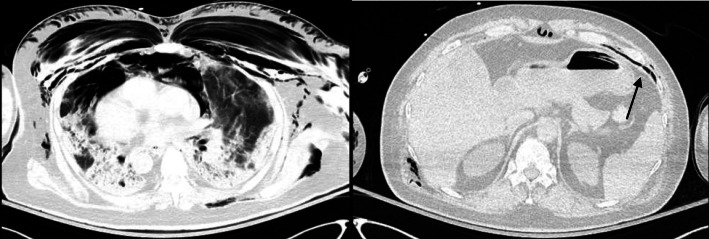

Fig. 4.

Computed tomography of the chest without contrast of Patient 2. A large pneumomediastinum and extensive soft tissue emphysema involving the anterior and posterior thorax (left). A tiny pneumoperitoneum in upper anterior abdomen (right)